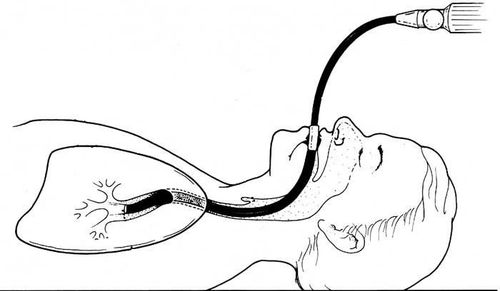

Nội soi phế quản đặt van một chiều là một loại phương pháp có mục đích giảm thể tích phổi bằng van một chiều từ hãng Pulmons X. Những chiếc van này sẽ được đặt vào trong lòng phế quản thông qua kỹ thuật nội soi phế quản bằng ống mềm.

Khi các van này đặt đúng vị trí, không khí sẽ đi ra theo một chiều duy nhất mà không cho phép không khí đi ngược vào lòng phế quản. Lâu dần thùy phổi sẽ xẹp xuống và nhờ đó giảm bớt thể tích phổi, hạn chế tình trạng căng phổi và cải thiện hiệu quả tình trạng hô hấp ở bệnh nhân bị bệnh phổi tắc nghẽn mãn tính có hiện tượng giãn phế nang nghiêm trọng.